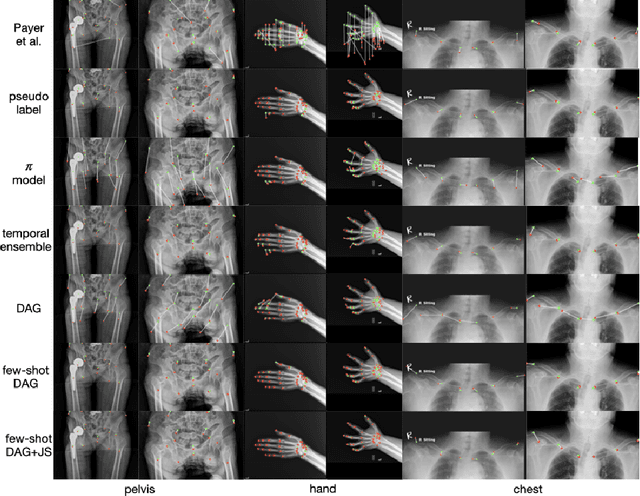

Abstract:Landmark localization plays an important role in medical image analysis. Learning based methods, including CNN and GCN, have demonstrated the state-of-the-art performance. However, most of these methods are fully-supervised and heavily rely on manual labeling of a large training dataset. In this paper, based on a fully-supervised graph-based method, DAG, we proposed a semi-supervised extension of it, termed few-shot DAG, \ie five-shot DAG. It first trains a DAG model on the labeled data and then fine-tunes the pre-trained model on the unlabeled data with a teacher-student SSL mechanism. In addition to the semi-supervised loss, we propose another loss using JS divergence to regulate the consistency of the intermediate feature maps. We extensively evaluated our method on pelvis, hand and chest landmark detection tasks. Our experiment results demonstrate consistent and significant improvements over previous methods.